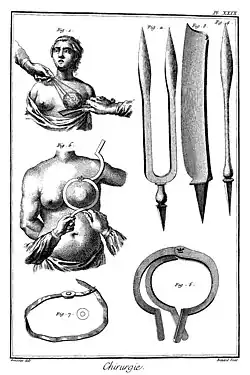

Entzündliche Brustleiden wie Abszesse wurden bereits in frühester Zeit mit dem Messer gespalten.[148] Die ersten Dokumentationen von Brustkrebserkrankungen stammen aus der Zeit von 2650 v. Chr. aus dem Alten Ägypten. Zu dieser Zeit wurden sie mit einem Brenneisen behandelt. Im Papyrus Edwin Smith (um 1600 v. Chr.) wurden acht Brustkrebserkrankungen beschrieben, auch die eines Mannes,[149] welche ebenfalls durch Kauterisation behandelt wurden. Der Papyrus Ebers enthält eine Beschreibung von Brustkrebs. Die Krebserkrankungen der Brust galten zur damaligen Zeit als nicht heilbar.[150][151][152]

Auch im Corpus Hippocraticum wurde der Fall eines Mammakarzinoms geschildert.[153] Von einer chirurgischen Behandlung tiefliegender Tumorerkrankungen wurde dort abgeraten, da nicht operierte Patienten länger lebten.[154]

Der griechische Arzt Galen sah Brustkrebs als Folge einer Säftestörung und damit als systemische Erkrankung, eine Krankheit des ganzen Organismus, an.[150][151] Als Mittel zur Behandlung wurden bis in das Mittelalter unterschiedlichste Rezepturen genutzt, um den als Ursache angesehenen eingedickten Körpersaft „Galle“ zu verflüssigen und abzuführen. Bestandteile waren, unter anderem, Blei- und Zinkkarbonat, Rosenöl und Hirschkot.[155] Die im Mittelalter durchgeführten Ätztherapien bei Carcinoma mammae oder dafür gehaltenen Brusterkrankungen wurden auch im 19. Jahrhundert noch durchgeführt, etwa mit Arsenik, Jod, Quecksilberpräpataten, Chlorzink[156] und Chlorkalipräparaten.[157]

Die erste Operation bei Brustkrebs soll Leonidas aus Alexandria um 100 n. Chr. durchgeführt haben. Zur Blutstillung und Entfernung von Tumorresten nutzte er ein Brenneisen.[155] Andreas Vesalius empfahl um 1543 bei Brustkrebs eine Entfernung der Brust (Mastektomie), bei welcher er jedoch eine Blutstillung mit Nähten der Kauterisation vorzog.[151]

Der französische Chirurg Jean-Louis Petit (1674–1750) legte das erste Konzept zur operativen Behandlung von Brustkrebs vor, welches jedoch erst 24 Jahre nach seinem Tode veröffentlicht wurde.[158] Sein Kollege Henry François Le Dran (1685–1770) meinte 1757, dass der Brustkrebs zumindest am Anfang lokaler Natur wäre. Erst wenn er sich seinen Weg in die Lymphbahnen geschaffen habe, sei die Prognose für die Patientin schlecht. Er entfernte daher die komplette Brust mitsamt den Lymphknoten der Achselhöhle.[158] Auch der schottische Chirurg Benjamin Bell (1749–1806) erkannte die Bedeutung einer Entfernung der Lymphknoten aus der Achselhöhle.[159]

Rudolf Virchow (1821–1902) konnte 1840 nachweisen, dass sich die Erkrankung aus den Epithelzellen entwickelt und sich entlang der Faszien und Lymphbahnen ausbreitet. Damit wandelte sich die Sicht vom Brustkrebs, welcher jetzt eher als lokale Erkrankung betrachtet wurde.[151][158]

Im Jahr 1867 stellte Charles H. Moore fest, dass die Ursache für ein Krebsrezidiv die unvollständige Entfernung des Primärtumors ist, und forderte daher bei Brustkrebs das benachbarte Gewebe (Haut, Lymphknoten, Fett, Pectoralismuskel) mitzuentfernen. Richard von Volkmann entfernte 1875 dementsprechend die Pectoralisfaszie mit.[160]

Diesem Konzept folgte auch William Stewart Halsted (1852–1922), der 1882 die erste radikale Mastektomie mit Entfernung der Faszie, der Brustmuskeln (Musculus pectoralis major, später auch in Anlehnung an eine von Willy Mayer vor der New Yorker Medizinischen Akademie vorgetragenen Methode den Musculus pectoralis minor[161]) und der Achsellymphknoten durchführte.[162] Für die damaligen Verhältnisse konnte damit eine lokale Tumorkontrolle mit einer 5-Jahres-Lokalrezidivrate von sechs Prozent erreicht werden.[163] Im deutschsprachigen Raum war Josef Rotter (1857–1924) Vorreiter dieser zum Standard gewordenen Methode, die er ab 1889 bei seinen Patientinnen durchführte.[164]

1874 beschrieb der englische Chirurg James Paget (1814–1899) eine ekzemartige Veränderung der Brustwarze mit angrenzendem duktalen Adenokarzinom, welche später als Morbus Paget bezeichnet wurde.[151]

Bis etwa 1884 glaubten manche Ärzte, dass Brustkrebs durch eine „Impfung“ mit Erysipelerregern erfolgreich behandelt werden könne.[157][165] Albert Schinzinger empfahl 1889 zur Behandlung inoperabler Mammakarzinom die Kastration.[166] Der schottische Chirurg George Thomas Beatson erkannte 1895, dass die Entfernung der Eierstöcke bei einer seiner Patientinnen den Brusttumor schrumpfen ließ.[150][151] 1897 wurde Brustkrebs erstmals bestrahlt.[155] Nachdem Hormone auch synthetisch hergestellt werden können, wurden auch endokrine Therapien[167] vermehrt eingesetzt.[131] Im Jahr 1927 wurde in Deutschland über die erste brusterhaltende Operation beim Mammakarzinom berichtet.[168]

1948 veröffentlichten David H. Patey und W. H. Dyson eine etwas weniger radikale Operationsmethode als Rotter und Halsted mit gleich guten Ergebnissen, bei welcher die Brustmuskeln erhalten bleiben konnten.[169] Sie wird heute noch als modifiziert-radikale Mastektomie nach Patey bezeichnet. Ein weiterer Rückgang der operativen Radikalität begann mit Robert McWhirter, der 1948 nach einfacher Mastektomie eine Strahlentherapie durchführte.[170] Einige Jahre nach der Entdeckung der Röntgenstrahlen wurden diese ab etwa 1900[171] auch zur Behandlung, von Brustkrebs eingesetzt, insbesondere zur (neoadjuvanten bzw. adjuvanten) Vor- oder Nachbestrahlung.[172][173]

Mit den Arbeiten von Bernhard und E. R. Fisher setzte sich in den 1960er Jahren die Auffassung durch, dass das Mammakarzinom schon im Frühstadium eine im Körper gestreute Erkrankung sein kann und die Lymphknoten keine Barriere gegen eine Ausbreitung im Körper darstellen. Vielmehr wurde der Befall der Lymphknoten als Indikator für eine systemische Ausbreitung angesehen. Die Lymphknotenentfernung hätte folglich nur prognostische und keine therapeutische Bedeutung.[174] Daher wurde das gängige Konzept der Operation und Strahlentherapie um eine anschließende Chemotherapie ergänzt, um auch Mikrometastasen zu vernichten.[175] Ab 1969 erfolgte die Chemotherapie als Kombination mehrerer Präparate mit Verbesserung der Wirksamkeit.[155]

Seit den 1970er Jahren werden Mammakarzinome zunehmend brusterhaltend operiert. Die Sentinel- oder auch Wächter-Lymphknoten-Entfernung erspart seit Ende des 20. Jahrhunderts oft die vollständige Entfernung der Lymphknoten aus der Achselhöhle. Damit wurde die operative Radikalität weiter reduziert.[158]